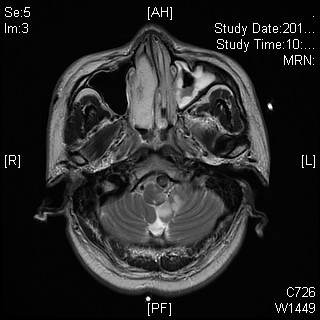

根据患者的情况,徐泉医生的带领下,对患者吞咽方面进行临床评估。评估发现,患者口腔期基本功能存在、唇舌力量较弱,协调性差;咽期咽反射消失、吞咽启动慢、喉上抬幅度小,速度慢、吞咽时有异常声音;饮水试验4级,无呛咳。患者自觉饮水全部下咽,咽部无残留,无呛咳感。因患者的病变位置,考虑存在环咽肌失迟缓可能,故进行电视透视检查。检查结果如下(视频1):患者会厌折返不全,咽缩肌无力,环咽肌失迟缓,咽部大量食物残留,存在隐形误吸等等。

根据检查结果,给予患者相关宣教,全面禁食水。经过分析,发现患者吞咽时,咽缩肌完全不收缩,不能形成压力差,食物无推动力。进一步探究咽缩肌损伤程度,给予患者食管高分辨测压检查,结果证实,患者在吞咽过程中咽缩肌几乎不收缩,而环咽肌松弛后残余压正常。综上,患者吞咽功能障碍的主要问题:会厌折返不全、咽缩肌无力。